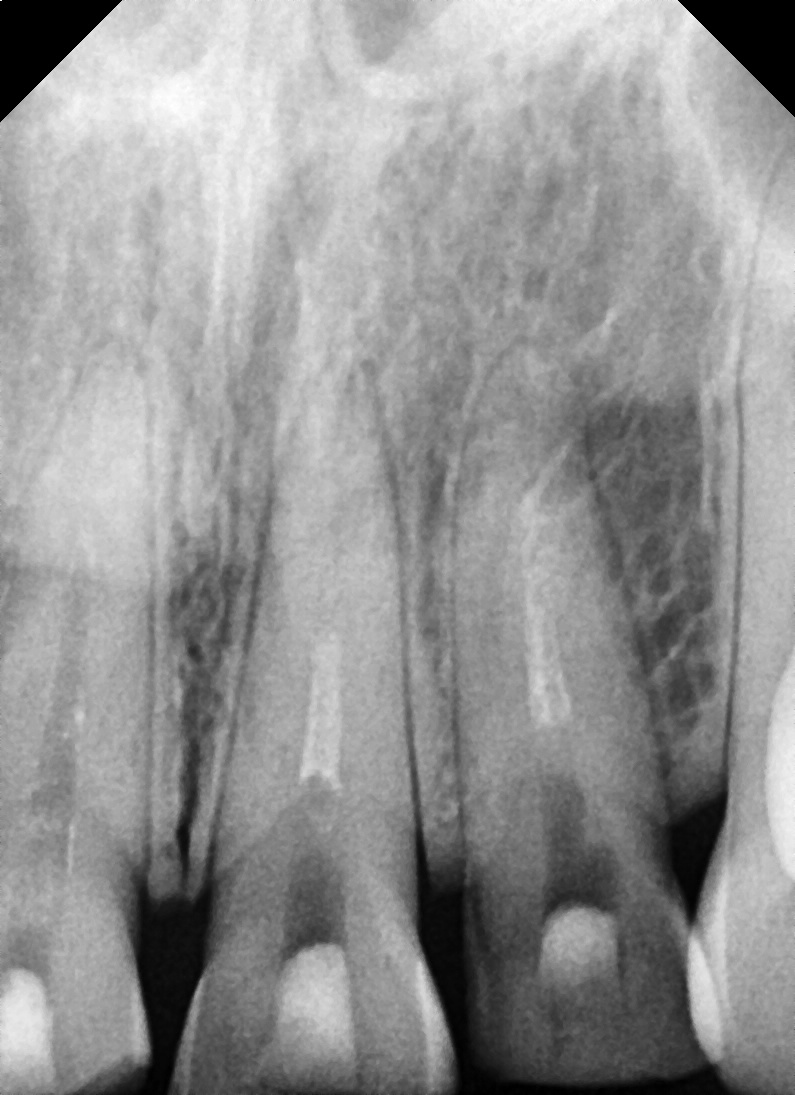

진단 결과

상악 앞니 4개 치아 파절 확인되었으며

일부 치아는 신경이 노출되어 신경치료 필요하고,

심한 변색과 파절로 인해 단순 레진 수복보다는

크라운 수복이 적합하다고 판단하였습니다.

① 신경치료

– 치아 내부에 염증과 손상된 신경을 제거하고,

치근관 치료를 통해 감염을 막았습니다.